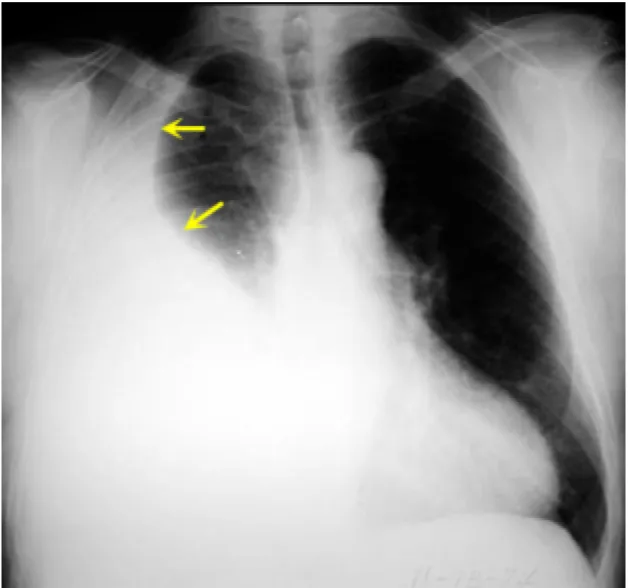

62세 여성이 10일 전부터 호흡곤란을 호소하며 내원하였다. 우측 가슴에 통증을 느끼며 마른 기침을 하고 있다. 혈압 128/82 mmHg, 맥박 82회/분, 호흡 22회/분, 체온 36.5℃로 측정되었다. 가슴 X선 사진을 찍었다. 이 환자의 진단은 무엇인가?

Imp: 흉막 삼출(pleural effusion)

• 가슴 X선 상 우측 폐의 opacity가 증가한 소견을 보이며, 기침할 때 통증을 느끼는 흉막 자극 증상을 보이고 있다.

• 현재 종격동이 음영의 반대측(좌측) 으로 편위된 것을 보아 흉막 삼출임을 알 수 있다.